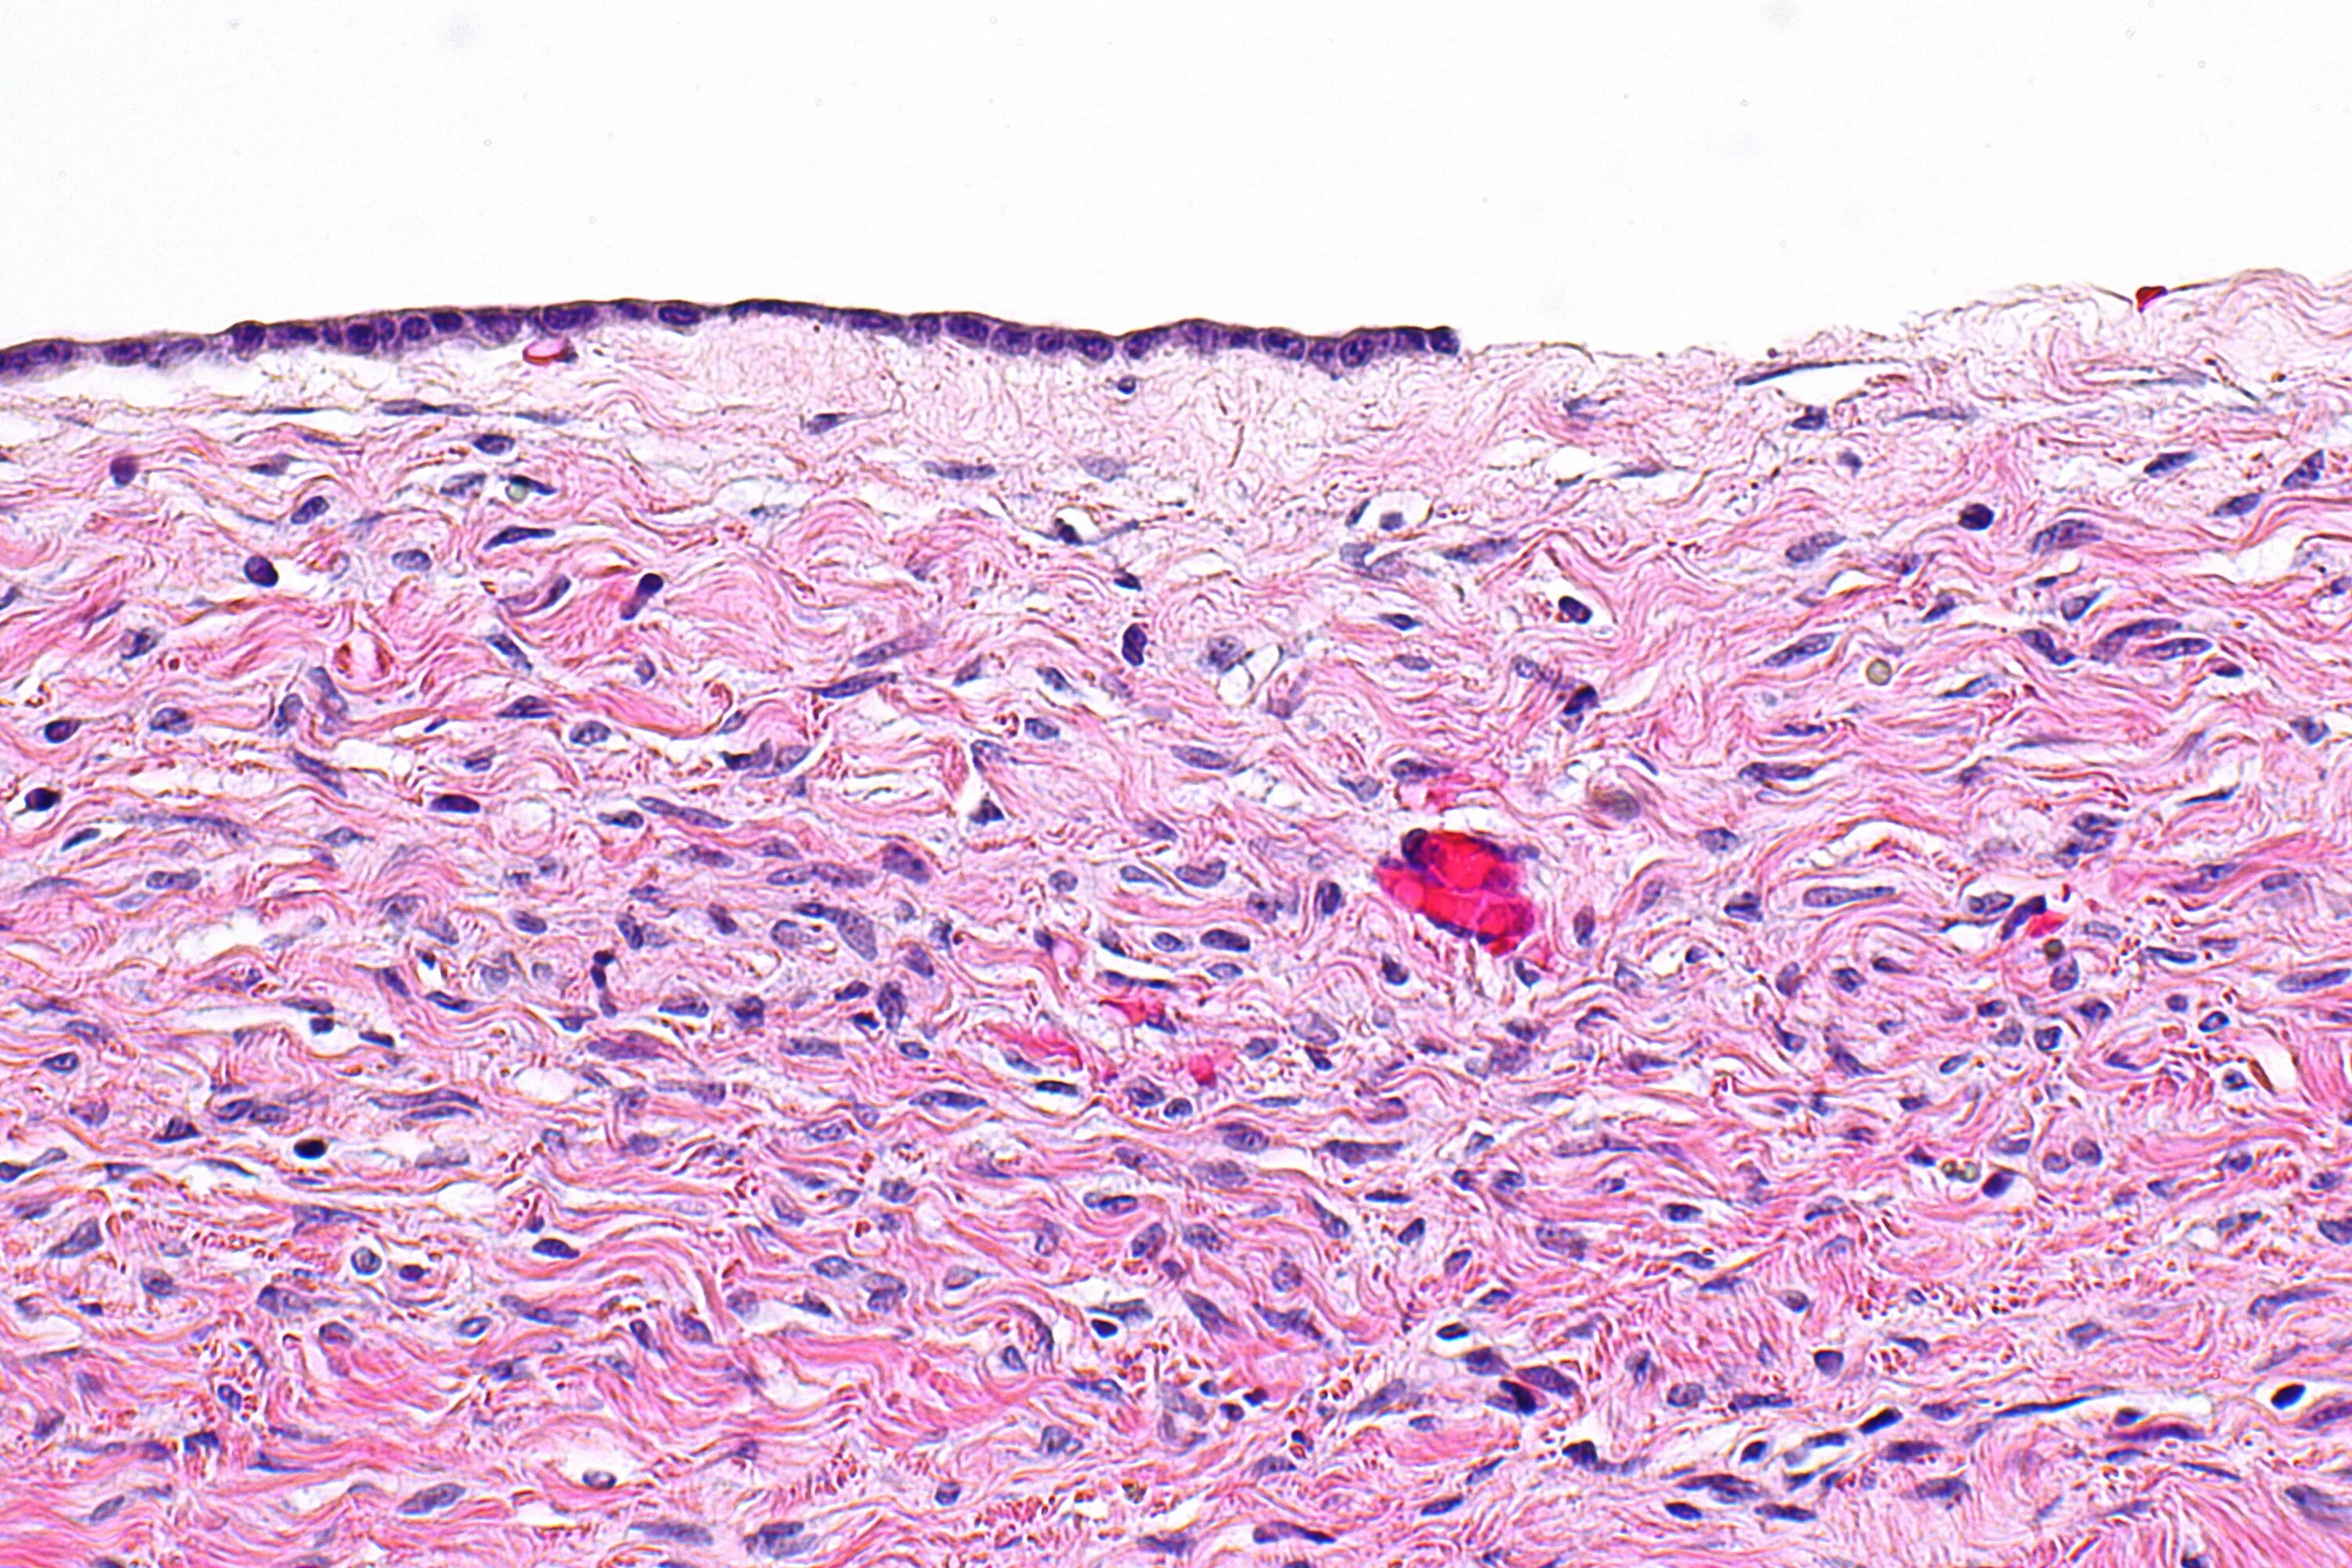

Что показала гистология замершей